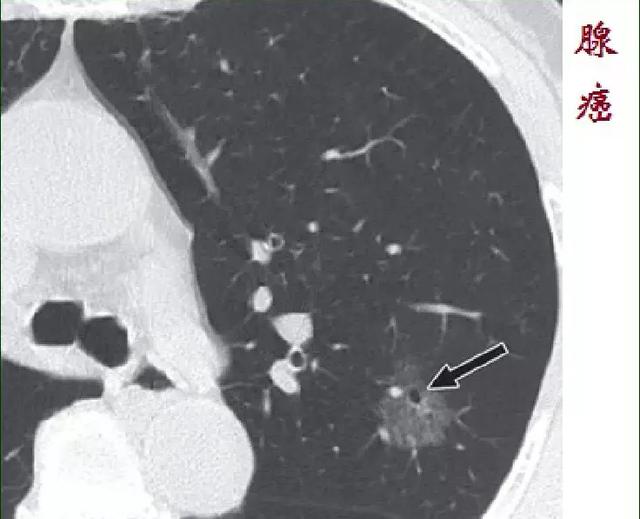

3.浸润性腺癌

大于15毫米。此时癌细胞继续增多增大,结节出现了明显的实性成分,并且突破了支气管的基底膜长到了血管和淋巴管里面去。